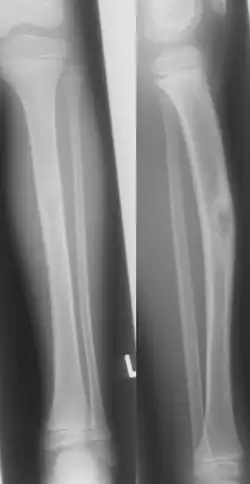

Die Diagnose ergibt sich neben der typischen Lokalisation aus dem Röntgenbild. Charakteristisch sind ventrale Kompaktaverdickung mit Auftreibung, den Markraum aussparende strähnige Spongiosklerosen Osteolyseherde umschließend mit insgesamt wabiger, randsklerosierter und scharf abgegrenzter Strukturveränderung.[4][7] In 20 % findet sich eine Zweitmanifestation an der Fibula.[7]